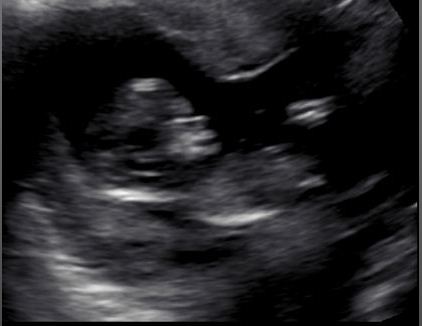

I hope you may be able to see a nub and be able to give me an idea of whether we have a pinkie or a bluey coming!! These pics were from about 12+5.